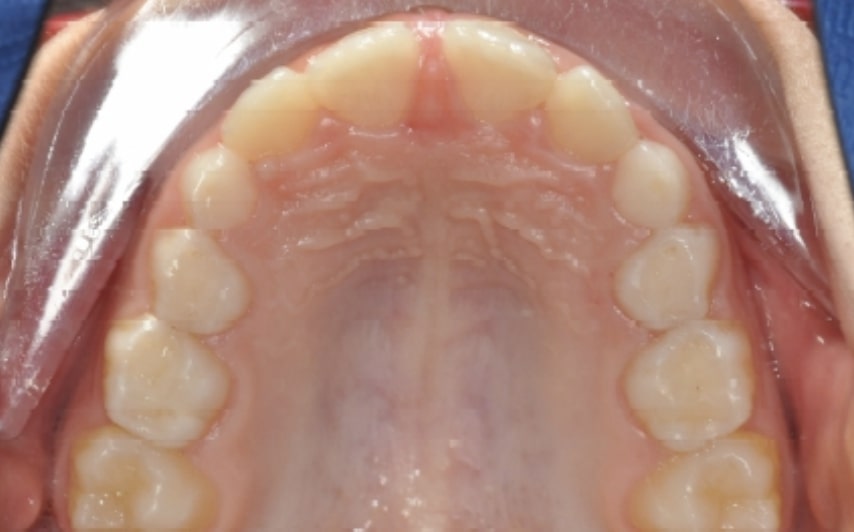

Malocclusion A6 Correction of Mandibular Retrusion in Growth phase patient | Skeletal Class II | Class II Division 1 malocclusion | Deep bite | Mixed dentition

SOFT TISSUES ANALYSIS: Upper Frenulum with low insertion

- Upper diastema (11-21)

- Reduced Transversal Diameters

- Upper Archform enlargement (dental expansion)